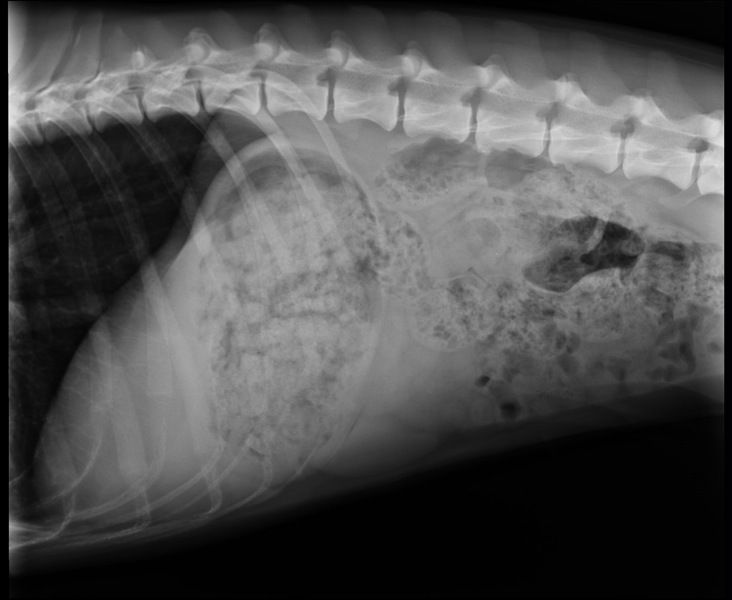

Seeing "the dip" provides some good info about her top line conformation. What I can now see is that the dorsal processes in her thoracic vertebrae are short. This is apparent from her flat withers and confirmed via the xray below which, by the way, clearly shows the T11 vertebra:

Image